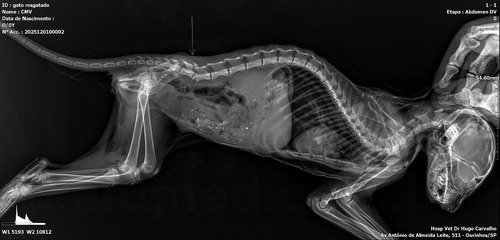

Deixo o raio x que foi feito hoje: